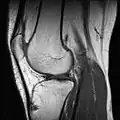

МРТ коленного сустава.

Применяются физикальные методы исследования: осмотр, пальпация, а также сбор анамнеза. Из инструментальных методов для визуализации изменений анатомических структур сустава большое распространение получило МР-исследование. Для оценки целостности и структуры костей, формирующих сустав, предпочтение отдаётся рентгенографии и компьютерной томографии. В настоящее время для диагностики применяют также артроскопию.